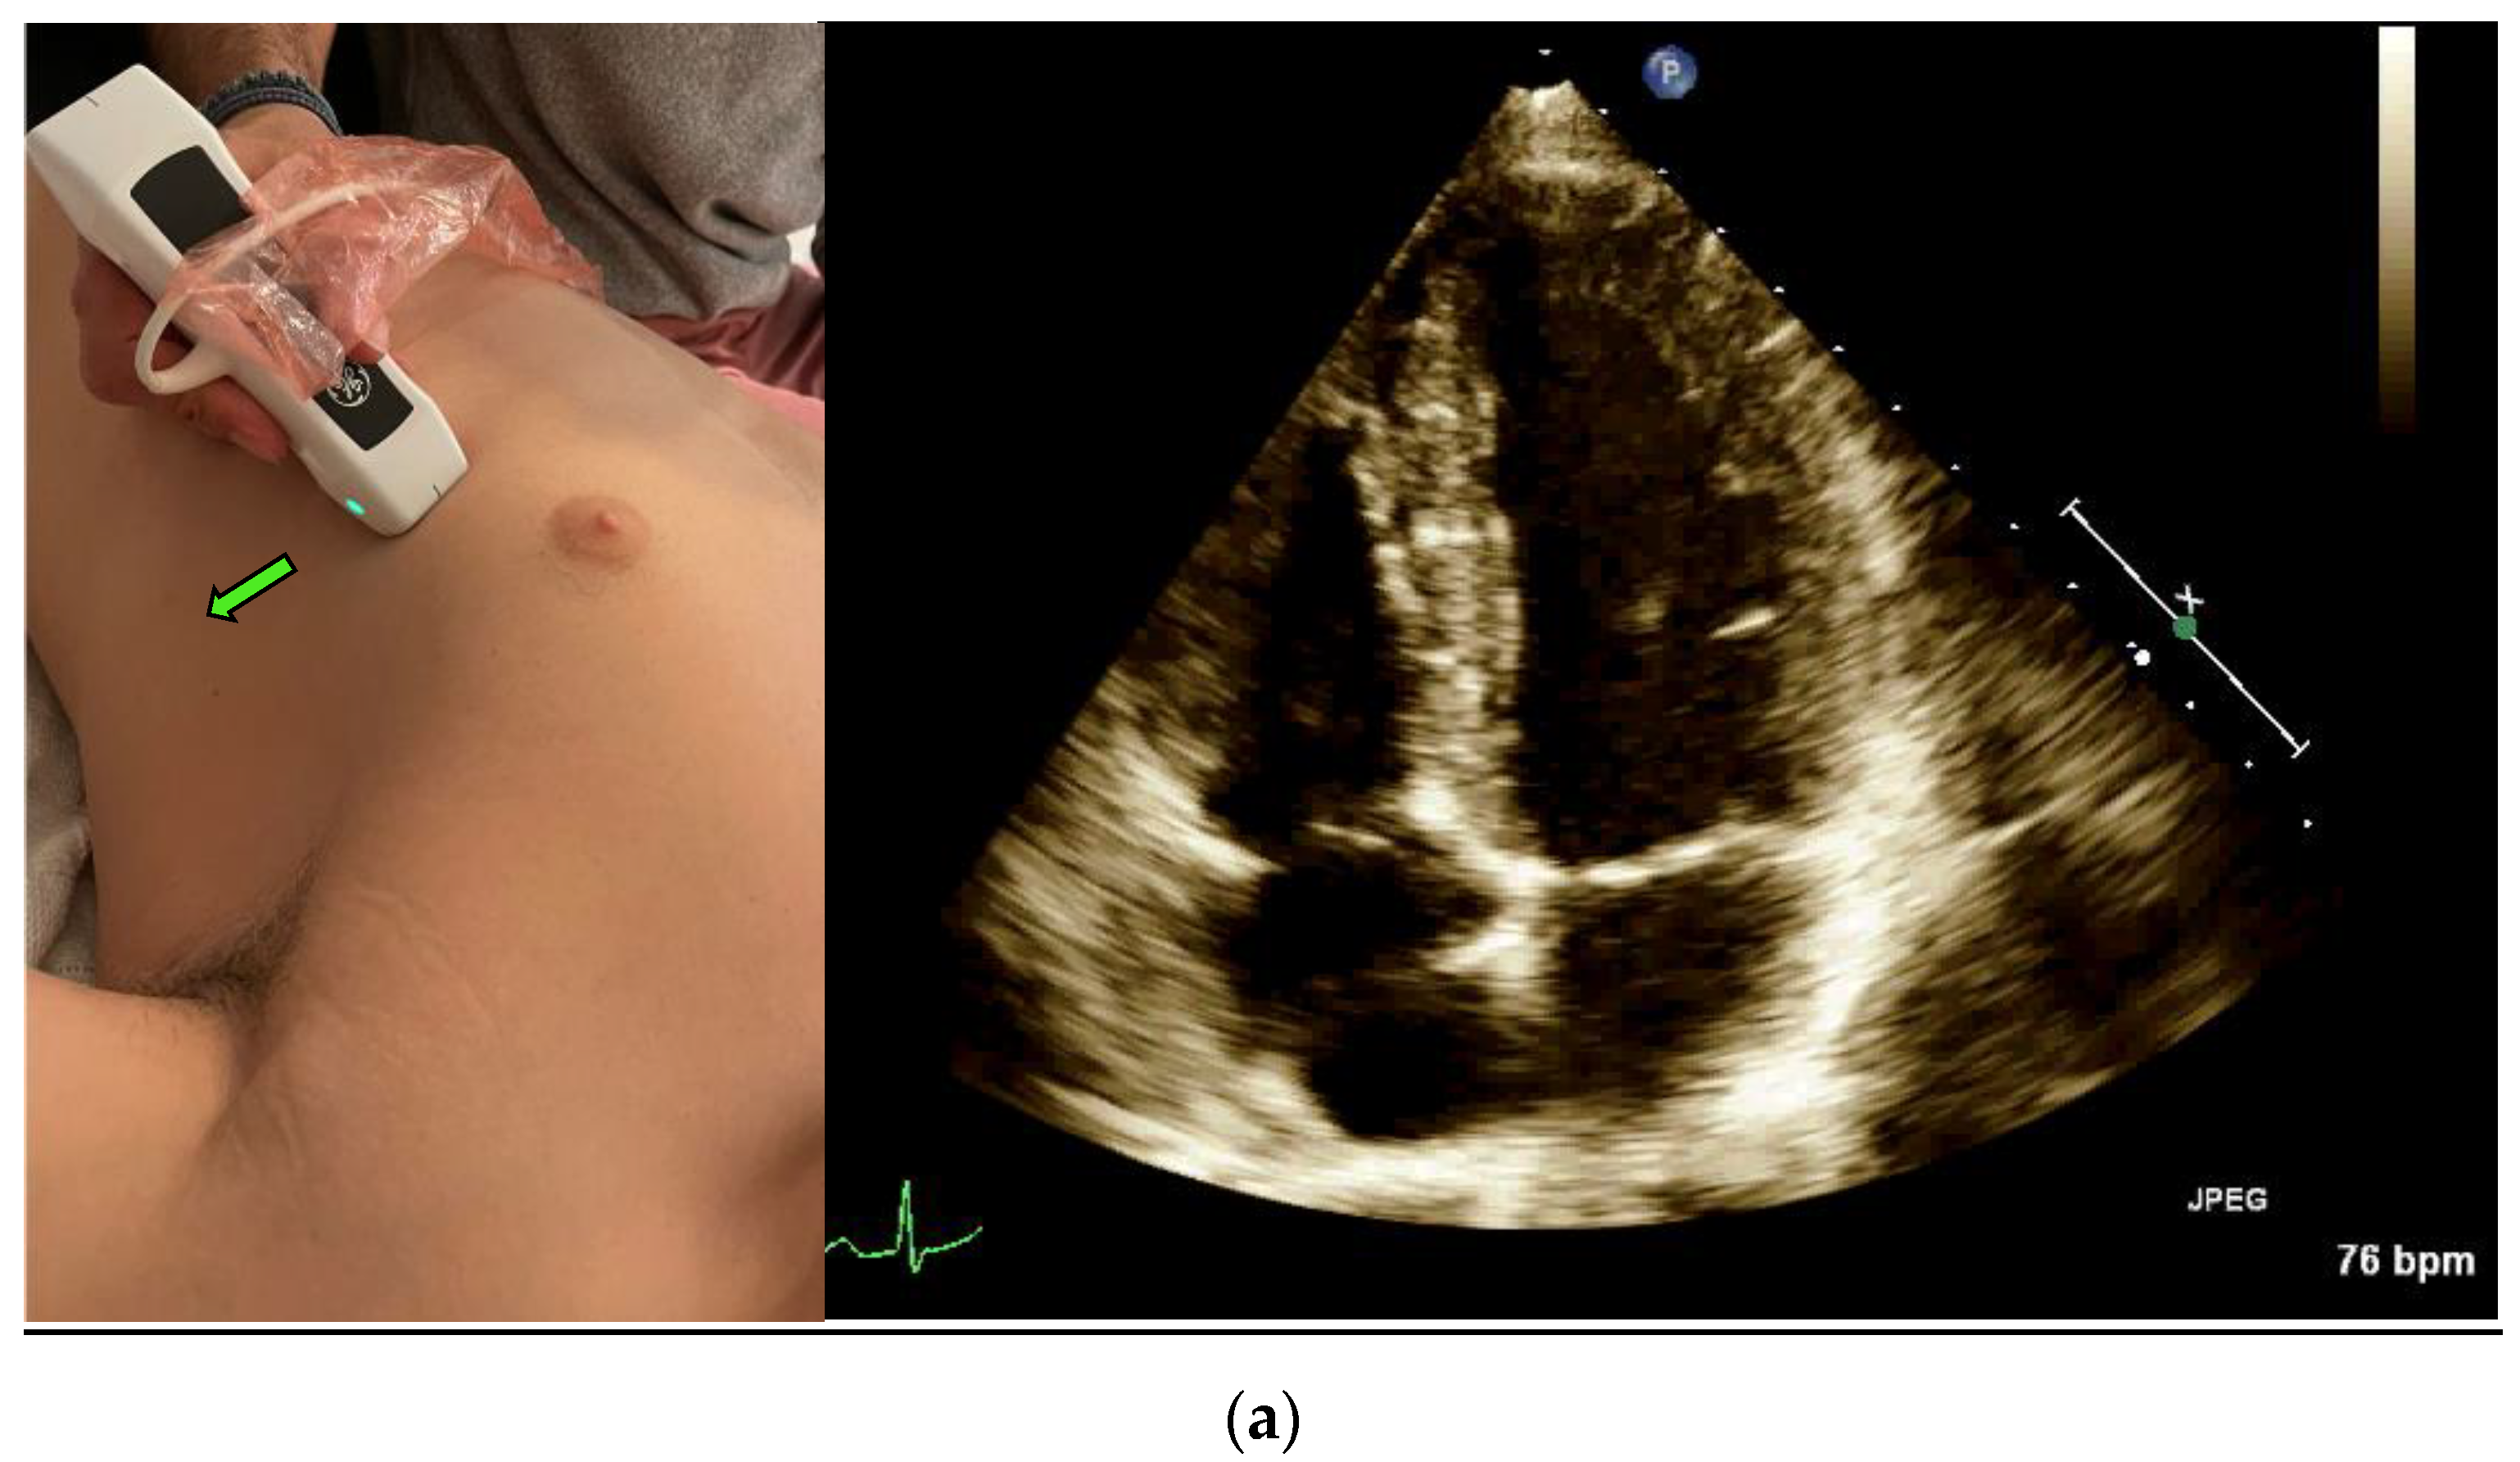

Left ventricular (LV) Ejection Fraction is an important clinical index. EF assessment can be extremely valuable in evaluating hemodynamically unstable patients [12] and dyspneic patients [4]. It can also diagnose heart failure in different settings, such as the emergency department and the internal wards [13,14]. The classic method for measuring EF is the Simpson method, which requires manually tracing the endocardial border of the left Ventricle in systole and diastole in both the apical four-chamber view (Figure 1a) and the apical two-chamber view (Figure 1c) [15].

The Velocity Time Integral (VTI) is classically measured at the apical five-chamber view (Figure 1b) by measuring the flow velocity through the left ventricle outlet (LVOT), which provides a velocity over time curve. Multiplying the VTI times the left ventricular outlet area equals the cardiac stroke volume, and if multiplied by the heart rate—the cardiac output [22]. The cardiac stroke volume aids in the differentiation of shock, shock treatment, determining fluid responsiveness, and in risk stratification [23,24]

3. Real-Time EF Measurement

A POCUS expert acquired apical four-chamber view (A4CV) clips by placing the probe horizontally over the apex of the heart (Figure 1a) and prospectively recording for at least 10 s. All clips were reviewed and blindly assessed for LVEF quantification by the Expert without exposure to the automatic tool results. Post hoc automatic analyses were performed and documented using the Venue™ real-time automatic LVEF. Each clip was considered an independent observation point.

5. VTI Measurement

An expert POCUS operator acquired the views by placing the probe horizontally in the apex of the heart and prospectively recording for at least 10 s in the apical five chambers view (Figure 1b). Half of the clips were scored by the physician to quality distribution from zero to two: 0—low for a failed attempt to obtain a proper reading of the VTI or image that could not be analyzed, 1—medium for VTI can be calculated but with moderate imaging quality and 2—high for good quality clips with a clearly demonstrated VTI. The clips were then blindly measured, tracing the LVOT velocity curve manually for VTI. The automatic tool measured the same clip, which similarly scored the clips according to imaging quality. High- or medium-quality clips were then further assessed and automatically calculated for LVOT VTI values. Each clip was considered an independent observation point.

Figure 1. (a) Acquisition and anatomy of the Apical Four Chamber View. (b) Acquisition and anatomy of the Apical Five Chamber View (similar acquisition to Apical Four Chamber View, with a slight upward tilt of the probe). (c) Acquisition (probe point—green arrow) and anatomy of the Apical Two Chamber View.